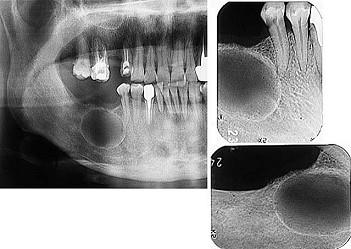

问题 发现下前牙变色,唇侧牙龈一肿物一月余,经X?线检查,结果如图。最可能的诊断是()

选项 A.根尖囊肿 B.牙龈瘤 C.根尖脓肿 D.成釉细胞瘤 E.牙骨质瘤

答案 A